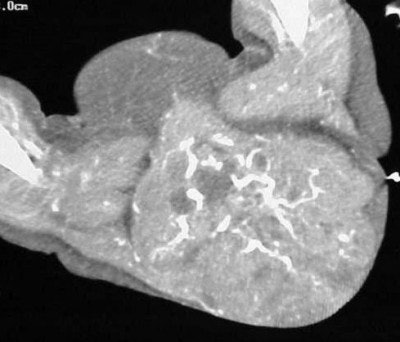

| Figure TC 3 |

![]() |

| Figure TC 4 |

In figure TC 3 we can see a large soft-tissue mass measuring approximately 9 cm wide by 6 cm in AP diameter, and 14 cm in height. It contains both fluid and semi-solid components of soft tissue as well as assorted calcifications. The mass appears to terminate (Figure TC 4) just above the level of the uterus (arrow).